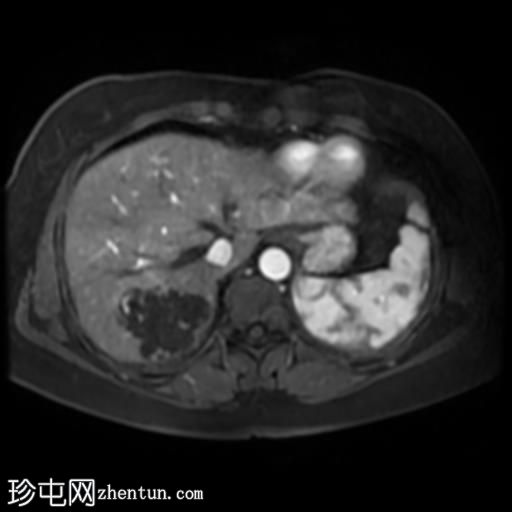

轴位T1加权像增强扫描

6.jpg

脂肪抑制动态增强扫描

肝脏第7段可见一边界清晰的分叶状肿块。T1加权像呈低信号,T2/T2脂肪抑制序列呈高信号,动脉期呈不连续结节状周边强化,门静脉期呈向心性强化,延迟期完全强化。DWI序列呈高信号,ADC值呈混合信号。